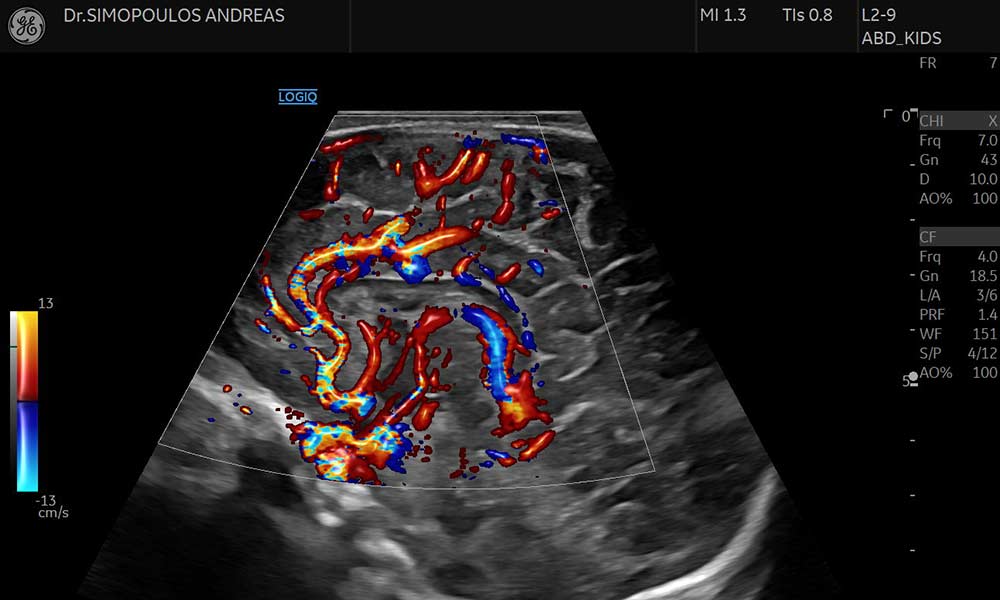

Εκτός από τις κλασικές μεθόδους (Color Doppler και Power Doppler), υπάρχει η δυνατότητα για πιο αντικειμενική τεχνική ανίχνευση της μικροαγγείωσης – MVI (Microvascular Imaging), τεχνική B-Flow, σε περιοχές ιδιαίτερα χαμηλών αιμοδυναμικών ροών καθώς και η νέα τεχνολογία Radiant Flow (Εξελιγμένη απεικόνιση έγχρωμου Doppler η οποία προσφέρει πληροφορία βάθους για την καλύτερη οριοθέτηση των αγγείων προσδίδοντας την αίσθηση της 3D απεικόνισης).